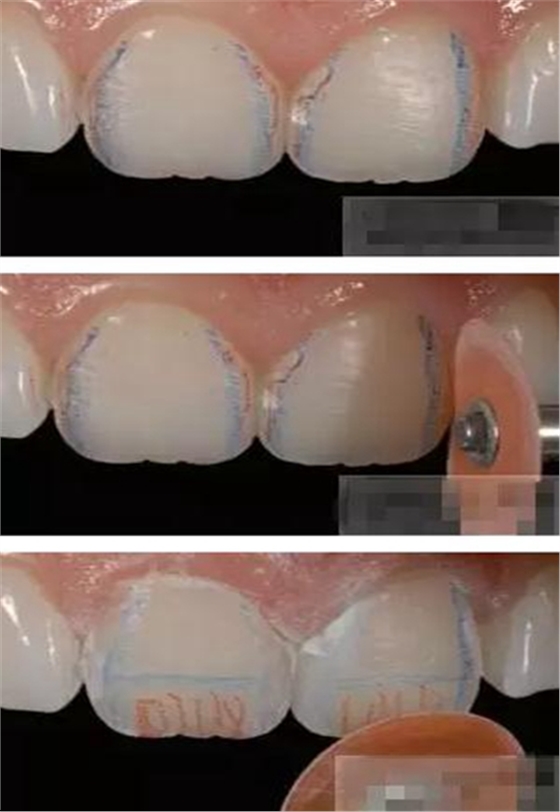

制作舌側(cè)背板

使用事先制作完成的硅橡膠模板。它是由技師在做好的美學(xué)蠟型的模型上制作的。這樣的方法為牙醫(yī)提供了許多便利:

a,美學(xué)蠟型可以使患者對(duì)可以達(dá)到的修復(fù)效果有直觀的了解,而且,患者也可以依據(jù)自己的美學(xué)素養(yǎng)對(duì)修復(fù)效果提出修改的意見;

b,應(yīng)用硅膠模板牙醫(yī)可以觀察到牙體預(yù)備量;

c,硅膠模板使牙體修復(fù)簡化,可以首先堆塑牙體的舌側(cè)面,這也是Dr.Vanini分層堆塑技術(shù)的基礎(chǔ),使用硅膠制作的膠刷會(huì)使堆塑更加簡單;